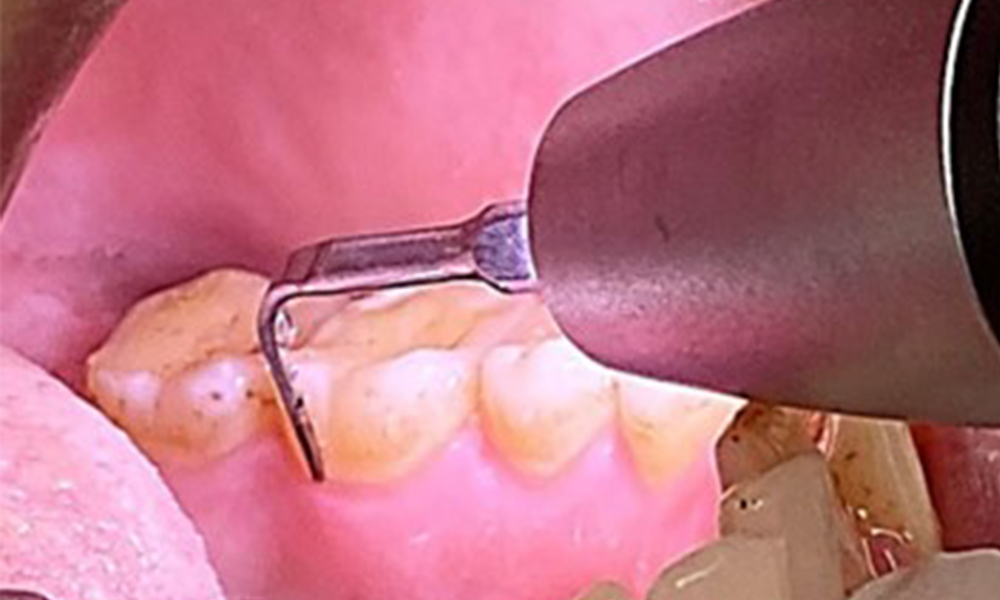

Due to the otherwise favourable general medical condition, the needs determined during the intraoral examination will be decisive for their treatment. It will be essential to periodically determine the probing depths. Gingival bleeding decreases in smokers, which is why the clinical diagnosis of periodontitis can only be made by probing (Fig. 7). Placing exclusive focus on the determination of bleeding indices may obscure existing periodontitis or gingivitis. (5)

- It is important to document findings during the therapeutic appointment. Bleeding-on-probing (BOP) status to measure periodontal pocket depth in the early stages of disease must be determined during each appointment. This is particularly important in smokers due to decreased tissue perfusion.